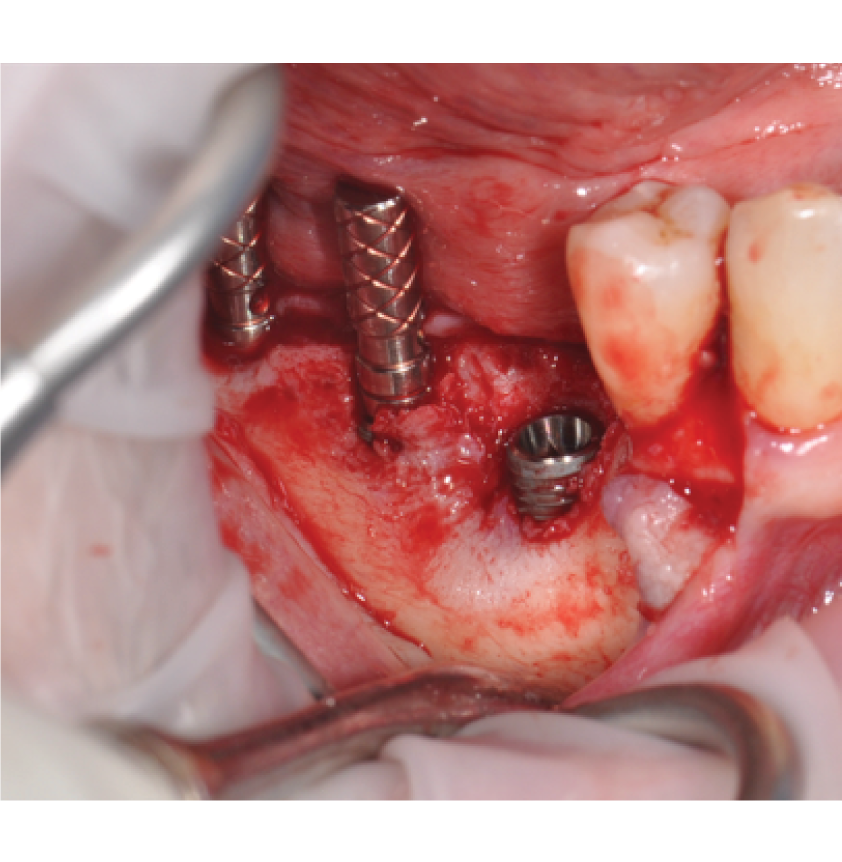

Director’s Clinical Cases

Director’s Clinical Cases

• Case presentations: Clinical pearl from real-world cases

• Autogenous none harvesting techniques

• Case Presentations: Clinical Pearl and must-know takeaways